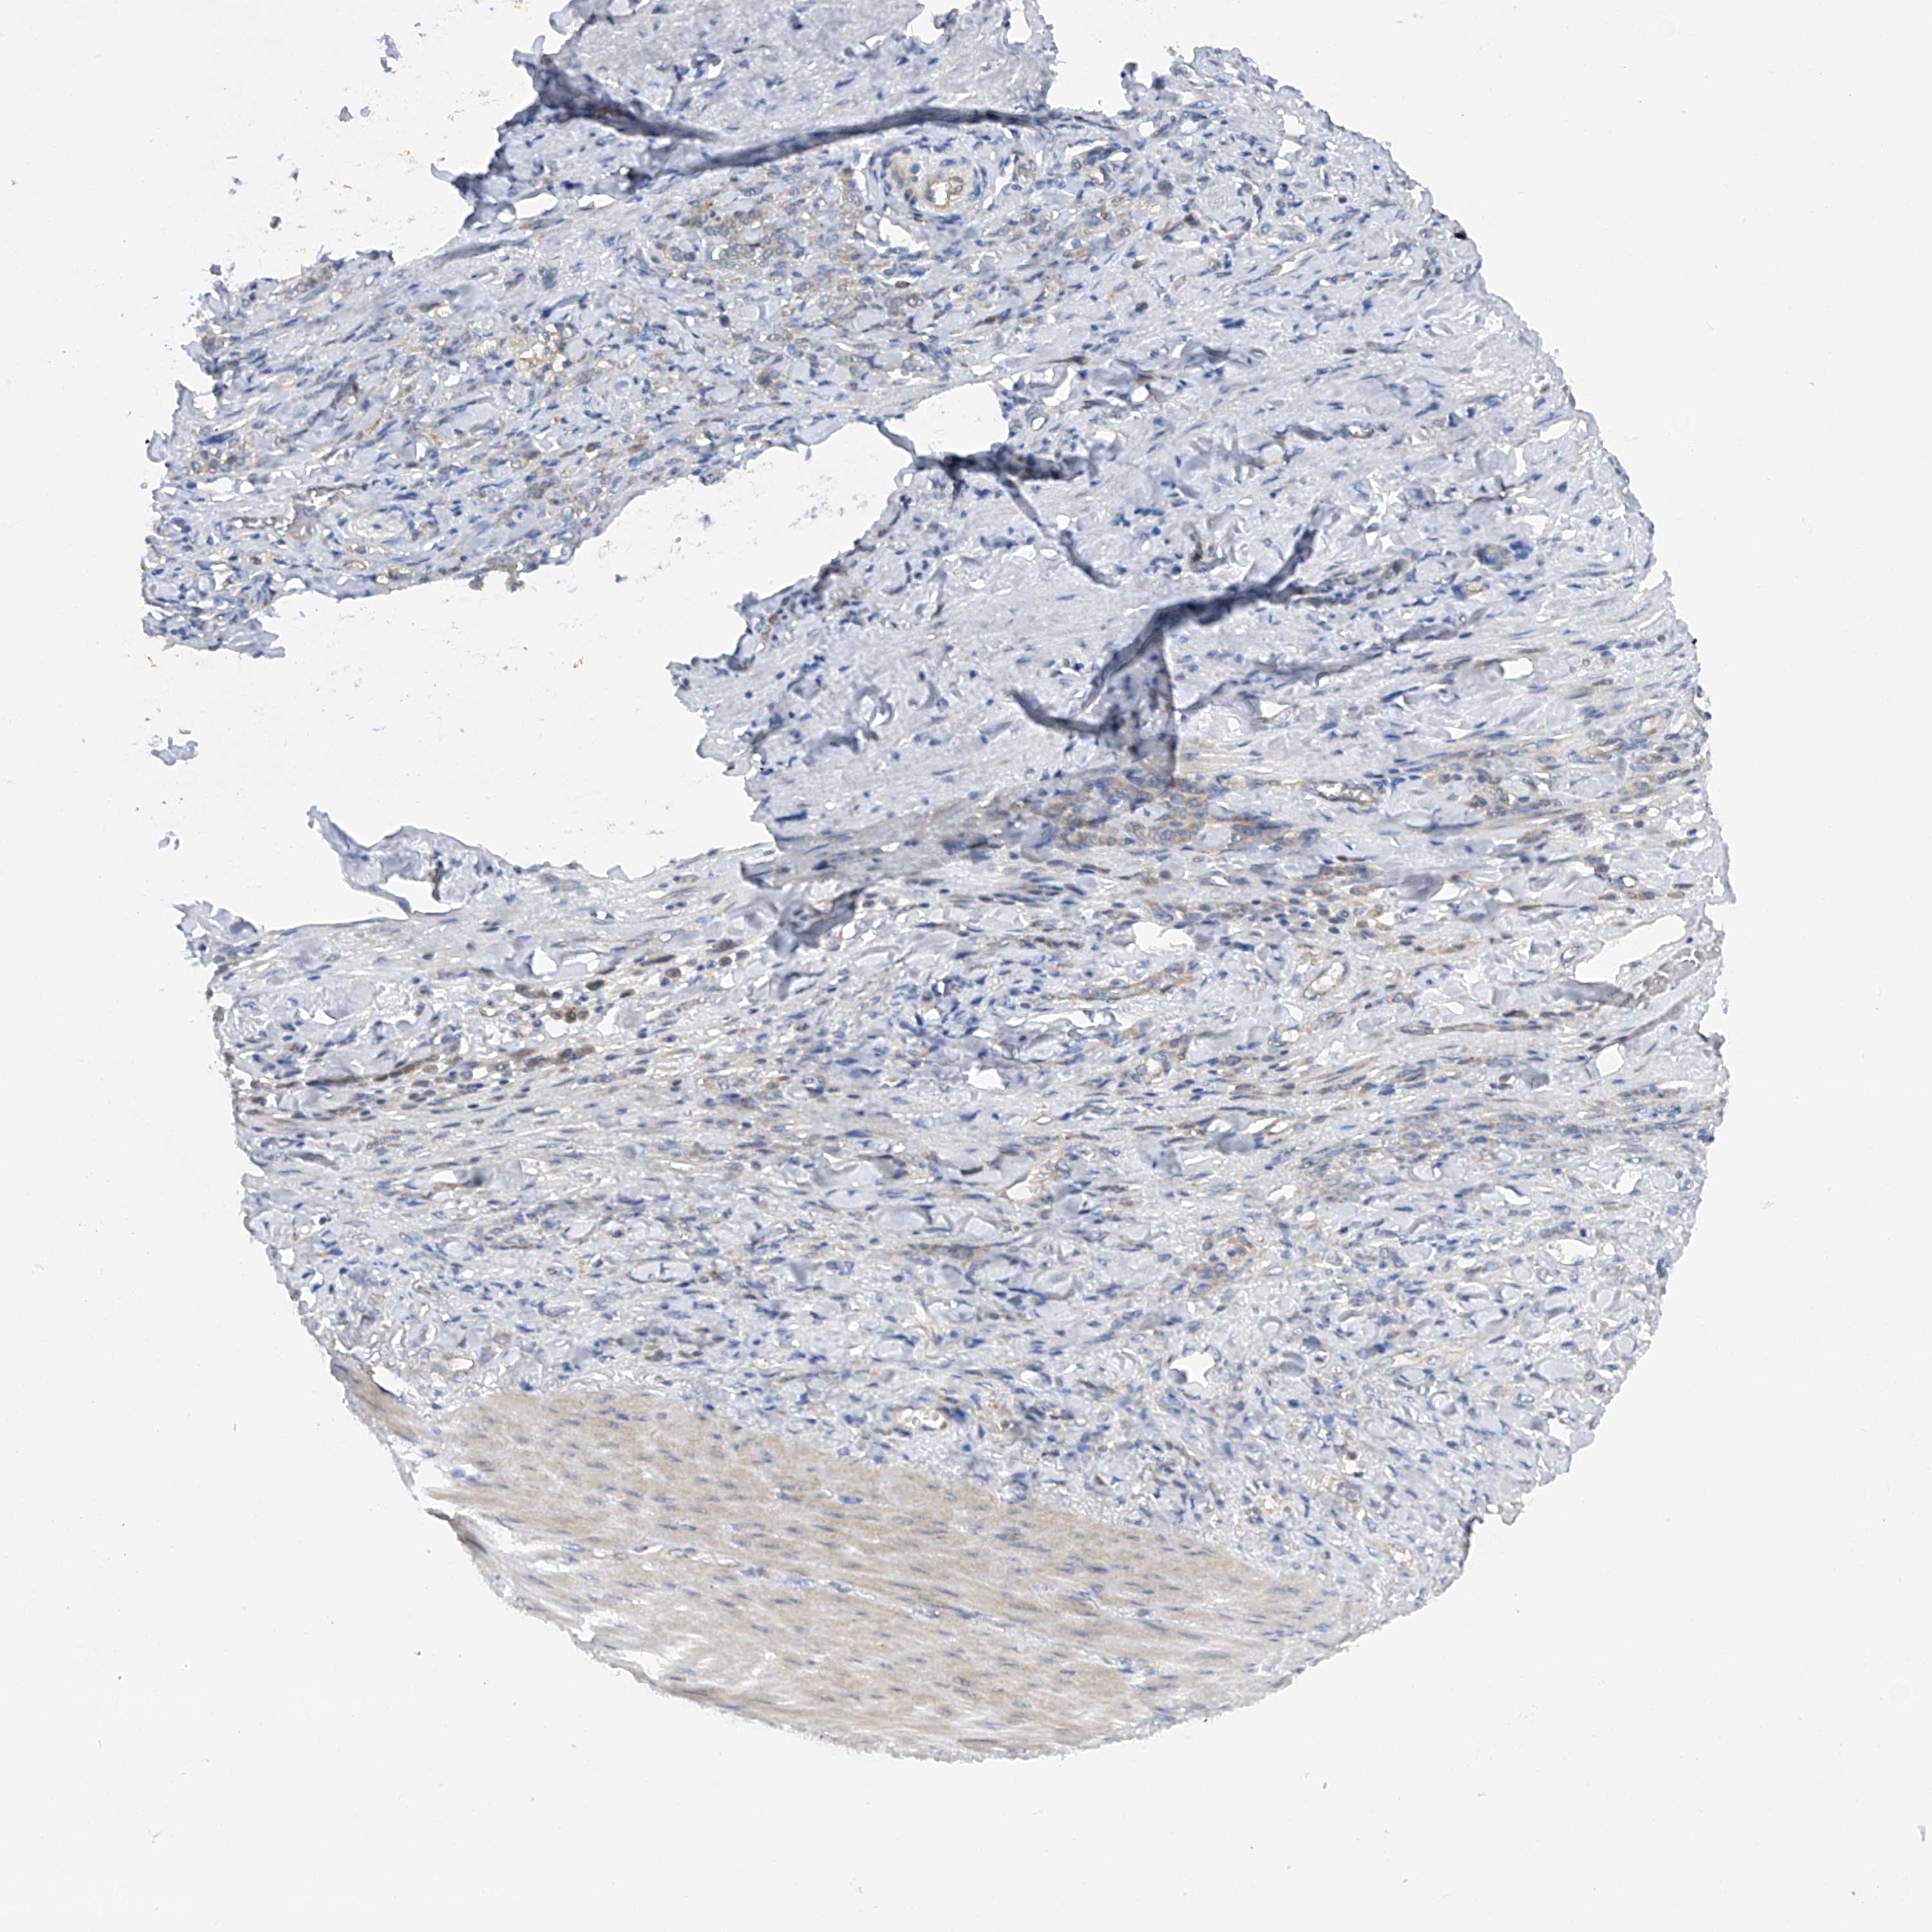

STOMACH CANCER - Protein expressioni

A mouse-over function shows sample information and annotation data. Click on an image to view it in a full screen mode. Samples can be filtered based on level of antibody staining by selecting one or several of the following categories: high, medium, low and not detected. The assay and annotation is described here.

Note that samples used for immunohistochemistry by the Human Protein Atlas do not correspond to samples in the TCGA dataset.

Antibody stainingi

Antibody staining in the annotated cell types in the current human tissue is reported as not detected, low, medium, or high, based on conventional immunohistochemistry profiling in selected tissues. This score is based on the combination of the staining intensity and fraction of stained cells.

Each image is clickable and will lead to virtual microscopy that enables deeper exploration of all samples and also displays staining intensity scores, fraction scores and subcellular localization as well as patient and tissue information for each sample.

Antibody HPA001842

Antibody CAB004036

Staining

High

Medium

Low

Not detected

Intensity

Strong

Moderate

Weak

Negative

Quantity

>75%

75%-25%

<25%

None

Location

Nuclear

Cytoplasmic/membranous

Cytoplasmic/membranous,nuclear

Adenocarcinoma, NOS

Adenocarcinoma, High grade